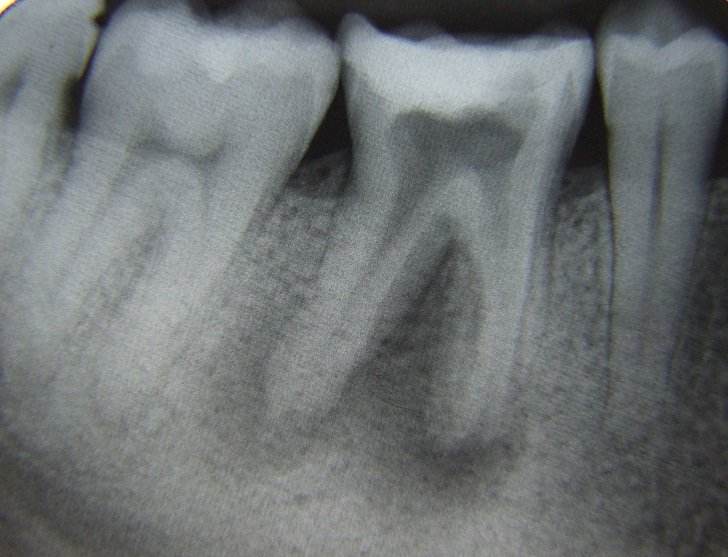

Desi nu este de dorit, uneori se constata prezenta unor leziuni extinse (granuloame, chisturi) care daca nu sunt rezolvate corespunzator, pun in pericol viabilitatatea dintelui.

Din nou tratamentul sub microscop optic efectuat de catre specialistii endodonti poate duce la salvarea dintelui.